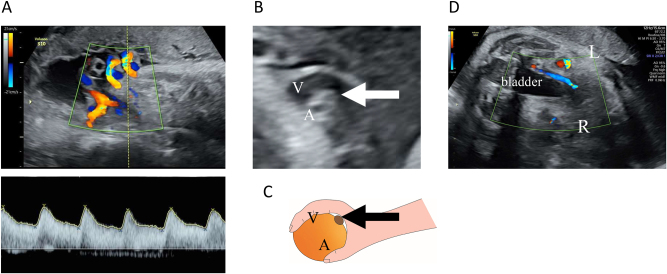

Case presentation: Initial patient screening at 30 weeks and 6 days of gestation revealed normal fetal development, with two umbilical arteries and one umbilical vein. However, at 34 weeks and 5 days of gestation, we observed reduced fetal movements and the absence of accelerations on cardiotocography. Subsequent color Doppler examination revealed cessation of blood flow across a broad area in one umbilical artery and a strongly curved umbilical vein surrounding the blood flow of the other artery. These formed the 'orange grab sign,' suggestive of UAT. Evaluations of blood flow in other areas revealed unremarkable findings. We performed an emergency cesarean section owing to fetal distress. The mother and newborn were healthy and discharged as healthy. The 1-month check-up revealed no abnormalities in the child. Pathological examination of the umbilical cord revealed fibrin-based thrombus formation along the length of one artery, confirmed to be an umbilical artery.

Conclusions: In the present case report, we presented the diagnostic challenges of UAT. Furthermore, we highlighted the need for timely intervention by comparing the number of umbilical vessels among previous ultrasound findings and verifying the presence of the 'orange grab sign.'